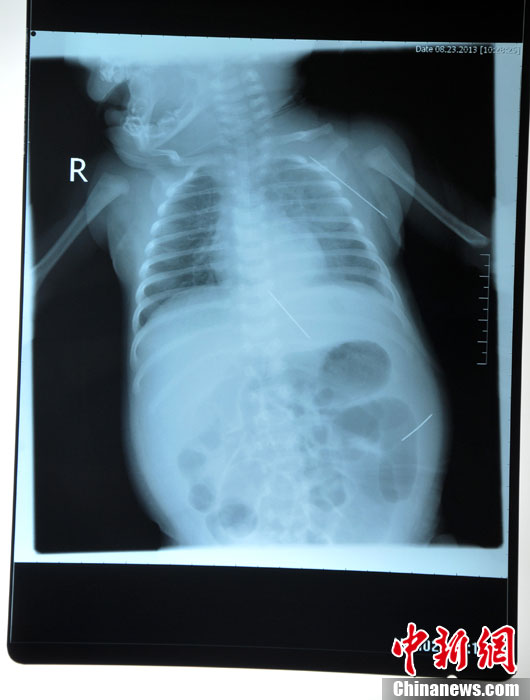

8月23日,黑龍江被“縫衣針”扎傷女嬰在哈爾濱醫(yī)科大學附屬第一醫(yī)院進行手術,成功取出三根長達4.5厘米的縫衣針,目前患兒正在術后觀察中,尚未脫離危險期。圖為三根鋼針在嬰兒體內(nèi)的各個位置。(哈爾濱醫(yī)大一院供圖)中新社發(fā)